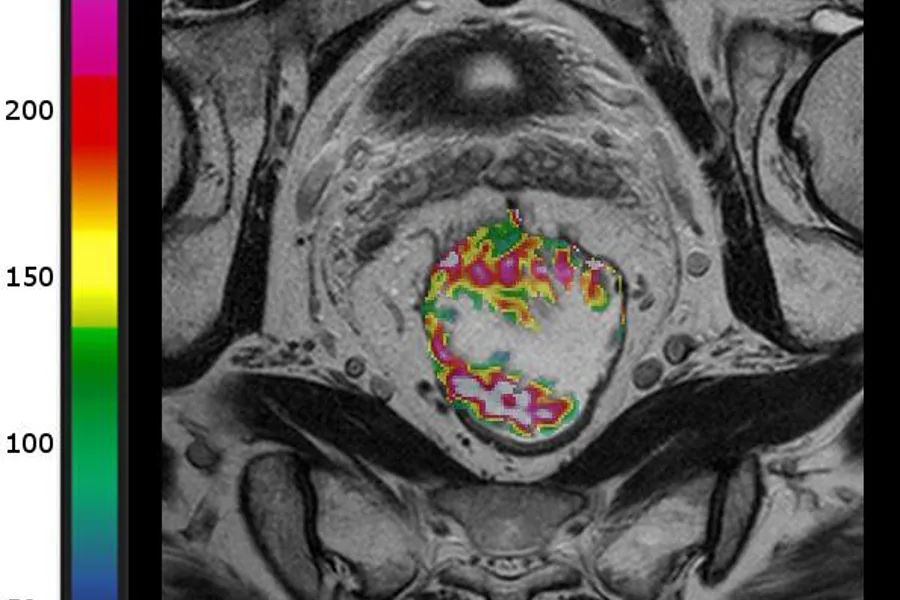

Her er MR-bilder av to ulike pasienter som har endetarmskreft i samme stadium. Den øverste har lav blodgjennomstrømning, og den nederste har høy. Den første ble diagnostisert med spredning til lever etter 12 måneder, mens den andre er sykdomsfri etter fem år. Kilde: Bakke et al. Radiology 2020